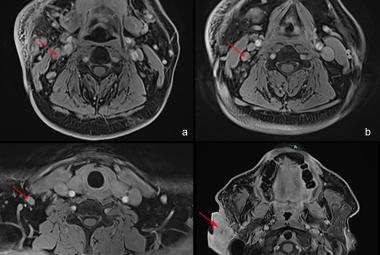

A delay in recognising acute posterior circulation infarct (POCI) can cause a delay in treatment and high mortality rate. There has been an increasing trend in incidence of stroke among the elderly. Treating acute stroke in elderly has been challenging due to the lack of data on the functional outcome and mortality risk. A 97-year-old woman had left sided weakness upon waking up from sleep and dizziness two days prior. Upon arrival, her Glasgow Coma Scale (GCS) was E3V4M6, BP 162/112 mmHg, NIHSS score 10, left sided power 3/5 and right sided power 4/5. Her computed tomography (CT) angiography brain showed P2 segment of right posterior cerebral artery and distal basilar artery thrombosis, with a posterior circulation territory mismatch. Thrombolysis was given immediately. She was discharged with NIHSS 5, GCS E4V5M6 and power bilateral limbs 4/5. She was put on lifelong Apixaban for stroke prevention and underwent post-stroke rehabilitation. The time of occlusion was decided based on the time a patient was last seen well. Studies have shown that patients aged 80 years and above presenting within 3-4.5 hours from symptoms, perform well with both intravenous thrombolysis and thrombectomy, with no increased risk for intracranial hemorrhage and death.

Kelewatan dalam mengenal pasti 'posterior circulation infarct' akut boleh menyebabkan kelewatan dalam rawatan dan kadar kematian yang tinggi. Terdapat peningkatan dalam kejadian strok di kalangan orang tua. Rawatan strok akut untuk orang tua sangat mencabar disebabkan oleh kekurangan data mengenai komplikasi dan hasil fungsi mereka. Seorang wanita berusia 97 tahun mengalami kelemahan di bahagian kiri badannya ketika bangun dari tidur dan pening dua hari sebelumnya. Apabila tiba di hospital, skala 'Glasgow Coma' (GCS) beliau adalah E3V4M6, tekanan darah 162/112 mmHg, skor NIHSS 10, kekuatan di bahagian kiri badan 3/5 dan di bahagian kanan badan 4/5. Pemeriksaan tomografi komputer (CT) otak menunjukkan trombosis pada segmen P2 arteri serebrum posterior sebelah kanan dan arteri basilar distal, dengan 'posterior circulation mismatch'. Trombolisis diberikan segera. Beliau dibenarkan discaj dengan NIHSS 5, GCS E4V5M6 dan kekuatan pada kedua-dua anggota badan 4/5. Beliau diberi Apixaban seumur hidup untuk pencegahan strok dan menjalani rehabilitasi pasa-strok. Masa thrombosis dianggarkan berdasarkan masa terakhir pesakit kelihatan sihat. Kajian telah menunjukkan bahawa pesakit yang berusia 80 tahun ke atas yang hadir ke hospital dalam masa 3-4.5 jam selepas gejala, menunjukkan pemulihan yang baik dalam aspek fungsi anggota badan jika dirawat dengan trombolisis intravena atau trombektomi, tanpa peningkatan risiko pendarahan otak dan kematian.